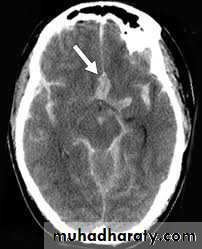

Non contrast high resolution CT scan which can demonstrate the amount of blood in the cisterns and fissure, ventricular size, associated intracranial hemorrhage, infarction and predict the location of aneurysm.

SeizureRebleeding, the major concern initially

Hydrocephalus ( usually obstructive by blood clot or communicating type which develop often late due to toxic effect of blood breakdown)